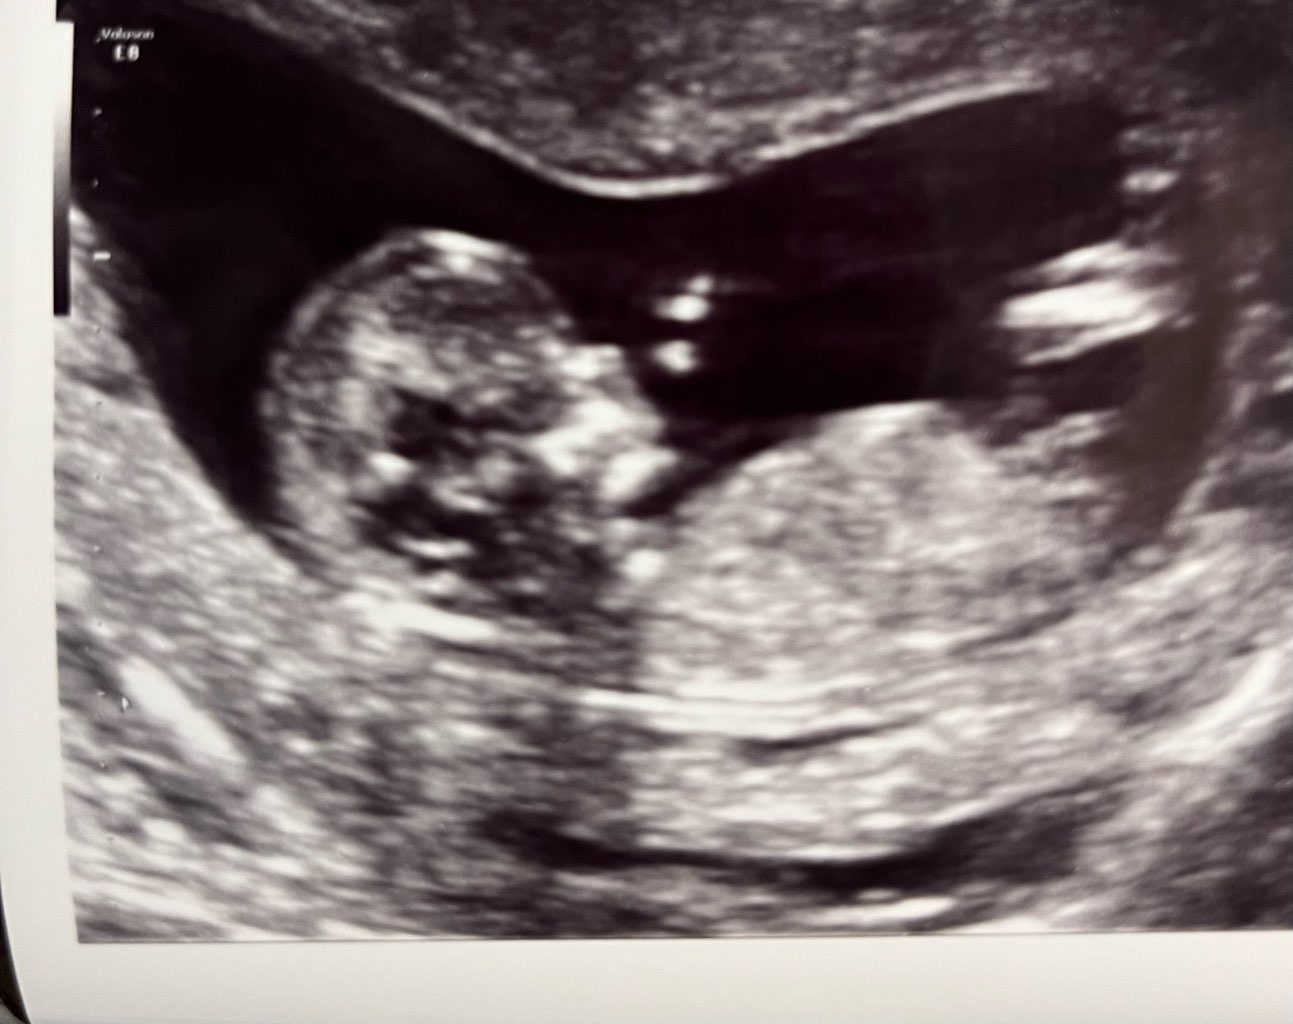

Cześć, jestem świeżo po badaniach prenatalnych, gdzie lekarz ocenił płeć dziecka w proporcjach 60% chłopiec, 40% dziewczynka, czyli wciąż niewiele wiem

I oczywiście wiem, ze jest jeszcze za wcześnie, aby to stwierdzić w 100%, nie oczekuje tez porady lekarskiej, tylko interpretacji, a nóż któraś z was się na tym zna